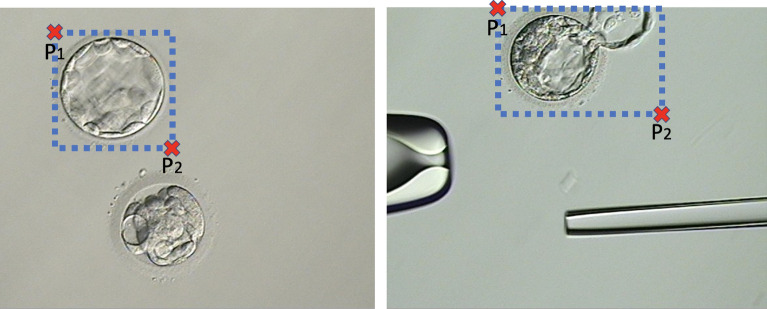

Apart from the embryo of interest, blastocyst micrograph images might contain other cells, or the instruments employed to manipulate them. Also, the blastocyst position on the image might not be centralized. Therefore, the first part of the pre-processing step consists of identifying the minimum region of the micrograph image that contains the blastocyst and excludes any extraneous objects.

For this procedure, we employed a python implementation to detect objects using a deep neural network architecture named“retinanet”25,26 (available at: https://github.com/fizyr/keras-retinanet). This network model is trained using a dataset of micrograph images where an expert has manually annotated two points and defining the best bounding box that contains the blastocyst of interest (Fig. 5). We employed a transfer learning approach27 to train the retinanet, which initializes the weights of the model with those obtained from the training with the ‘imagenet’database28. Then the network training was performed using our blastocyst micrograph database for 50 epochs of 1,000 steps each. These parameters were manually set ensuring that the epochs vs. accuracy/loss (learning) graph reach a plateau.

Figure 5.

Examples of two blastocyst micrographs and the bounding pox defined by and .

After training, the network model was capable of automatically defining the best bounding box for any input image containing a blastocyst. Using these values, we can automatically crop the original image to obtain an image O with the blastocyst centrally located and contained within the minimum area (smallest possible rectangle).